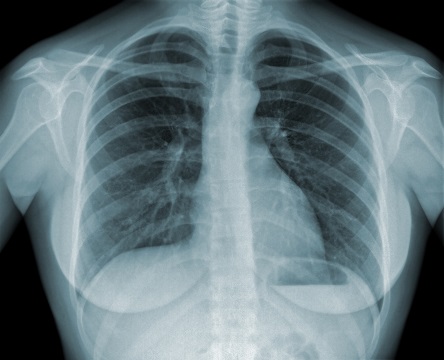

其实,一旦出现以下症状,就应及时到医院就诊,进行胸片或低剂量胸部CT检查,排除肺结核的可能。